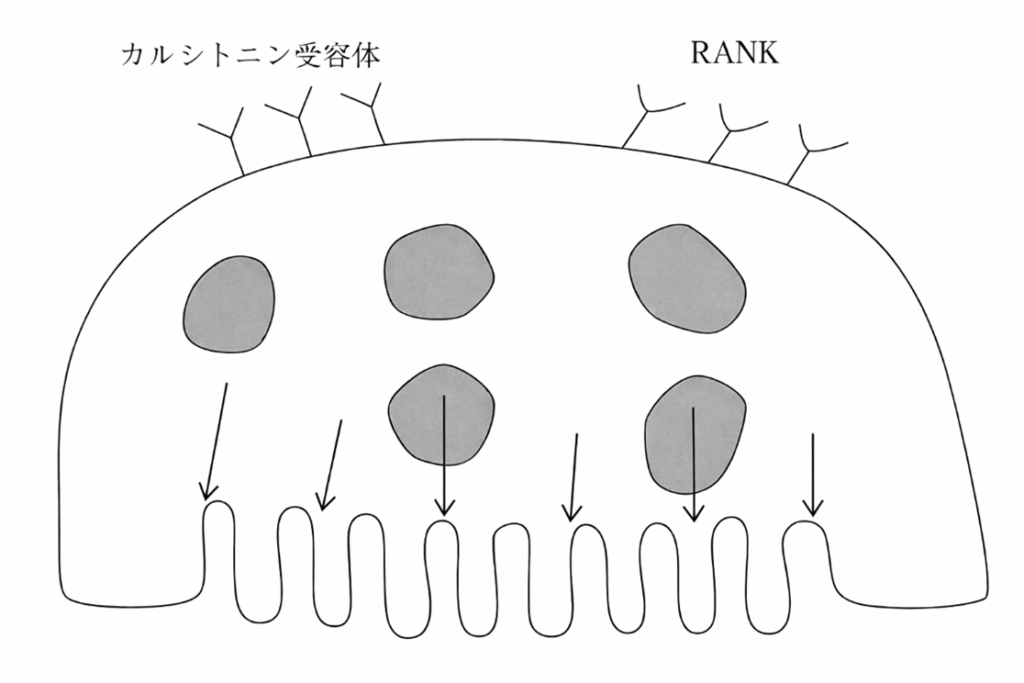

午前-8

破骨細胞を模式図に示す。矢印で示す部位から分泌されるのはどれか。1つ選べ。

a. H+

b. Ca2+

c. HCO3―

d. HPO42-

解答を見る

a